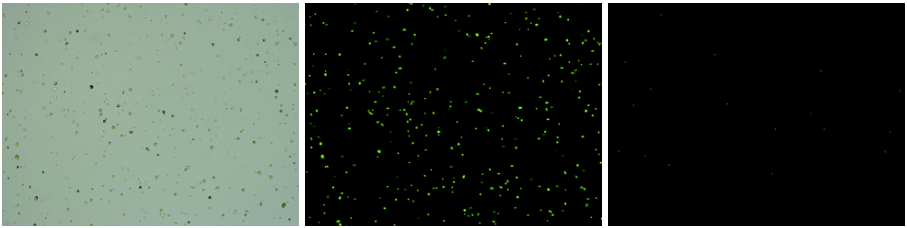

人腎組織樣品,細(xì)胞活率:97.86%,結(jié)團(tuán)率:8.68%